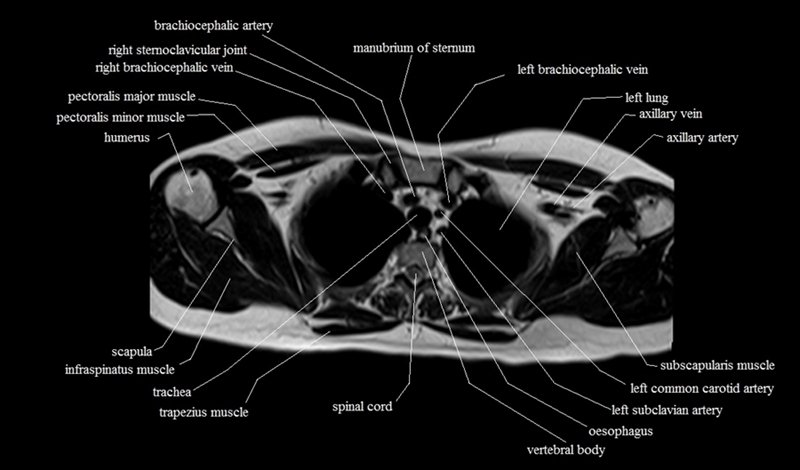

MRI Axial Cross Sectional Anatomy of Chest

This MRI chest (thorax) axial cross sectional anatomy tool is absolutely free to use. Use the mouse scroll wheel to move the images up and down, or alternatively, use the tiny arrows (→) on both sides of the image to navigate through the images. For a more detailed view, double-click the image to view it in full screen, and use the menu in the top right-hand corner to view individual slides or play them in a loop.